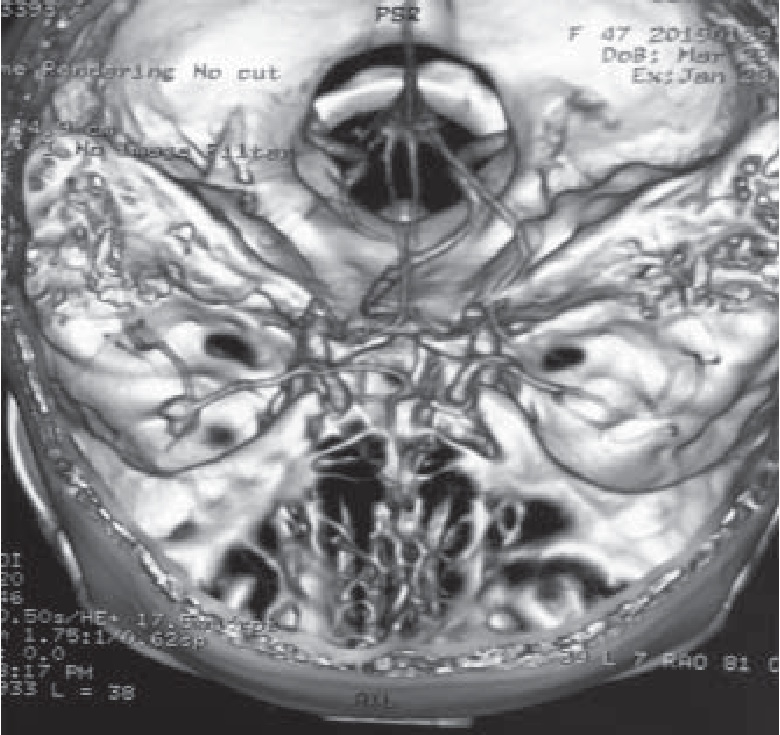

Выполнена КТ головы в ангиорежиме. Заключение: КТ-картина мешотчатой аневризмы правой срединной мозговой артерии (рис. 4.). Субарахноидальное кровоизлияние в височно-теменной области справа и затылочной доле справа, в теменной доле слева, по намету мозжечка, в заднем роге левого бокового желудочка в полости четвертого желудочка и цистерн четверохолмия. Неравномерное пристеночное утолщение слизистой оболочки в обеих верхнечелюстных пазух, в клетках решетчатого лабиринта, в основной пазухе с наличием небольшого количества тяжистого содержимого в правой половине основной пазухи.

Рис. 4. КТ-картина мешотчатой аневризмы правой срединной мозговой артерии